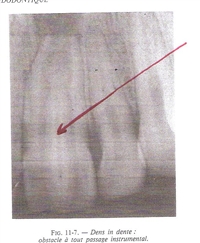

Invagination dentaire : c’est la ‘dens in dente » caractéristique de la « mésiodens » vue avec les dents surnuméraires.

Une petite dent surnuméraire pousse à l'intérieure de la pulpe d'une dent.

Une petite dent surnuméraire pousse à l’intérieure de la pulpe d’une dent.